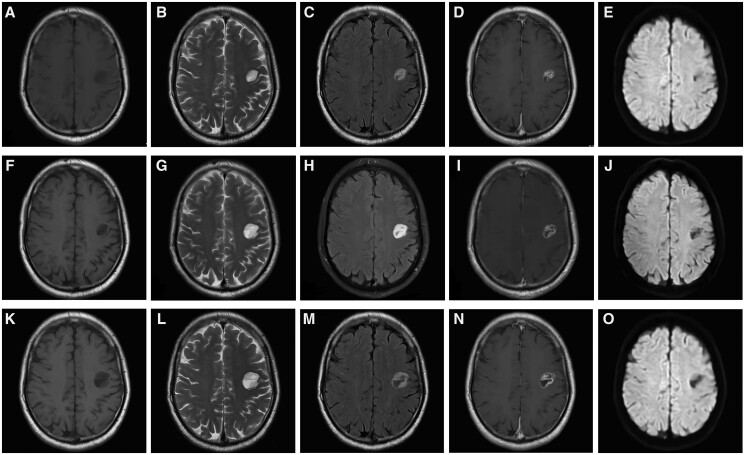

Myxoid glioneuronal tumour (MGNT), previously described as dysembryoplastic neuroepithelial tumour of the septum pellucidum, was classified as a new tumour type in the fifth edition of the WHO Central Nervous System Tumor Classification of 2021. This classification was based on its anatomical location, imaging features, and genetic characteristics. MGNTs are clinically rare and prone to misdiagnosis. In this report, we present a case of MGNT in the left frontal lobe, which was confirmed through surgical pathology.